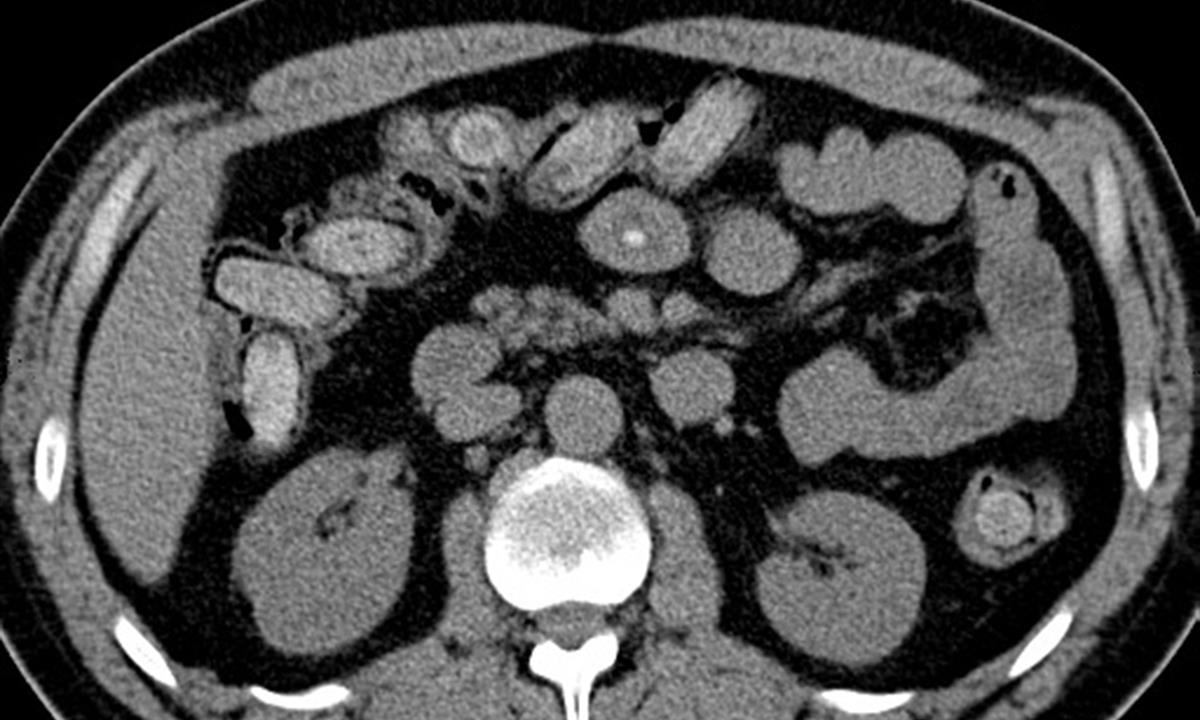

Celníci muže zadrželi a převezli na odborné lékařské vyšetření – počítačovou tomografii (CT). Snímky z CT prokázaly, že se v jeho břišní dutině nacházejí desítky kapslí o velikosti 2x5 cm s neznámým obsahem.

Již během sobotní noci vyšlo na speciální toaletě z těla pašeráka prvních 26 kapslí obsahujících kokain. Další kapsle vycházely postupně v následujících dnech, poslední v úterý večer. Dnešní kontrolní CT vyšetření potvrdilo, že se v jeho tělních dutinách již žádné kapsle nenacházejí.